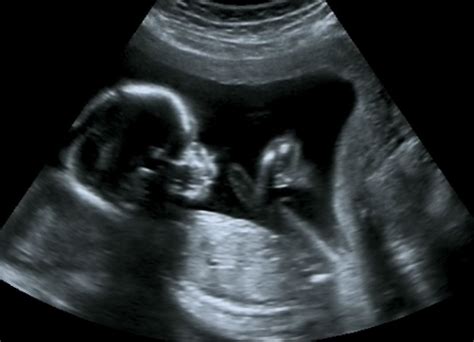

30 Week Ultrasound Image

• Assess Baby's Growth: The ultrasound helps measure the baby's size, including the head circumference, abdominal circumference, and femur length. These measurements are compared to standard growth charts to ensure the baby is developing normally.

• Ultrasound Procedure: The technician will use a transducer to move over your abdomen, capturing images of the baby. You may be asked to change positions to get better views.